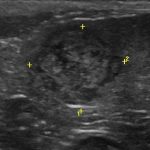

2017年8月21日 / 最終更新日 : 2025年6月27日 武内どうぶつ病院 症例報告 脾臓の腫瘍(過形成・血腫・血管肉腫など) 脾臓は、肝臓や腎臓と違って、少しなじみの薄い臓器かもしれません。 特に年齢が増すと、臓器の腫瘍は増えてくる傾向にあります。多くの場合外からでは臓器の腫大には全くと言っていいほど気づきません。ましてや元気や食欲などの症状も […]